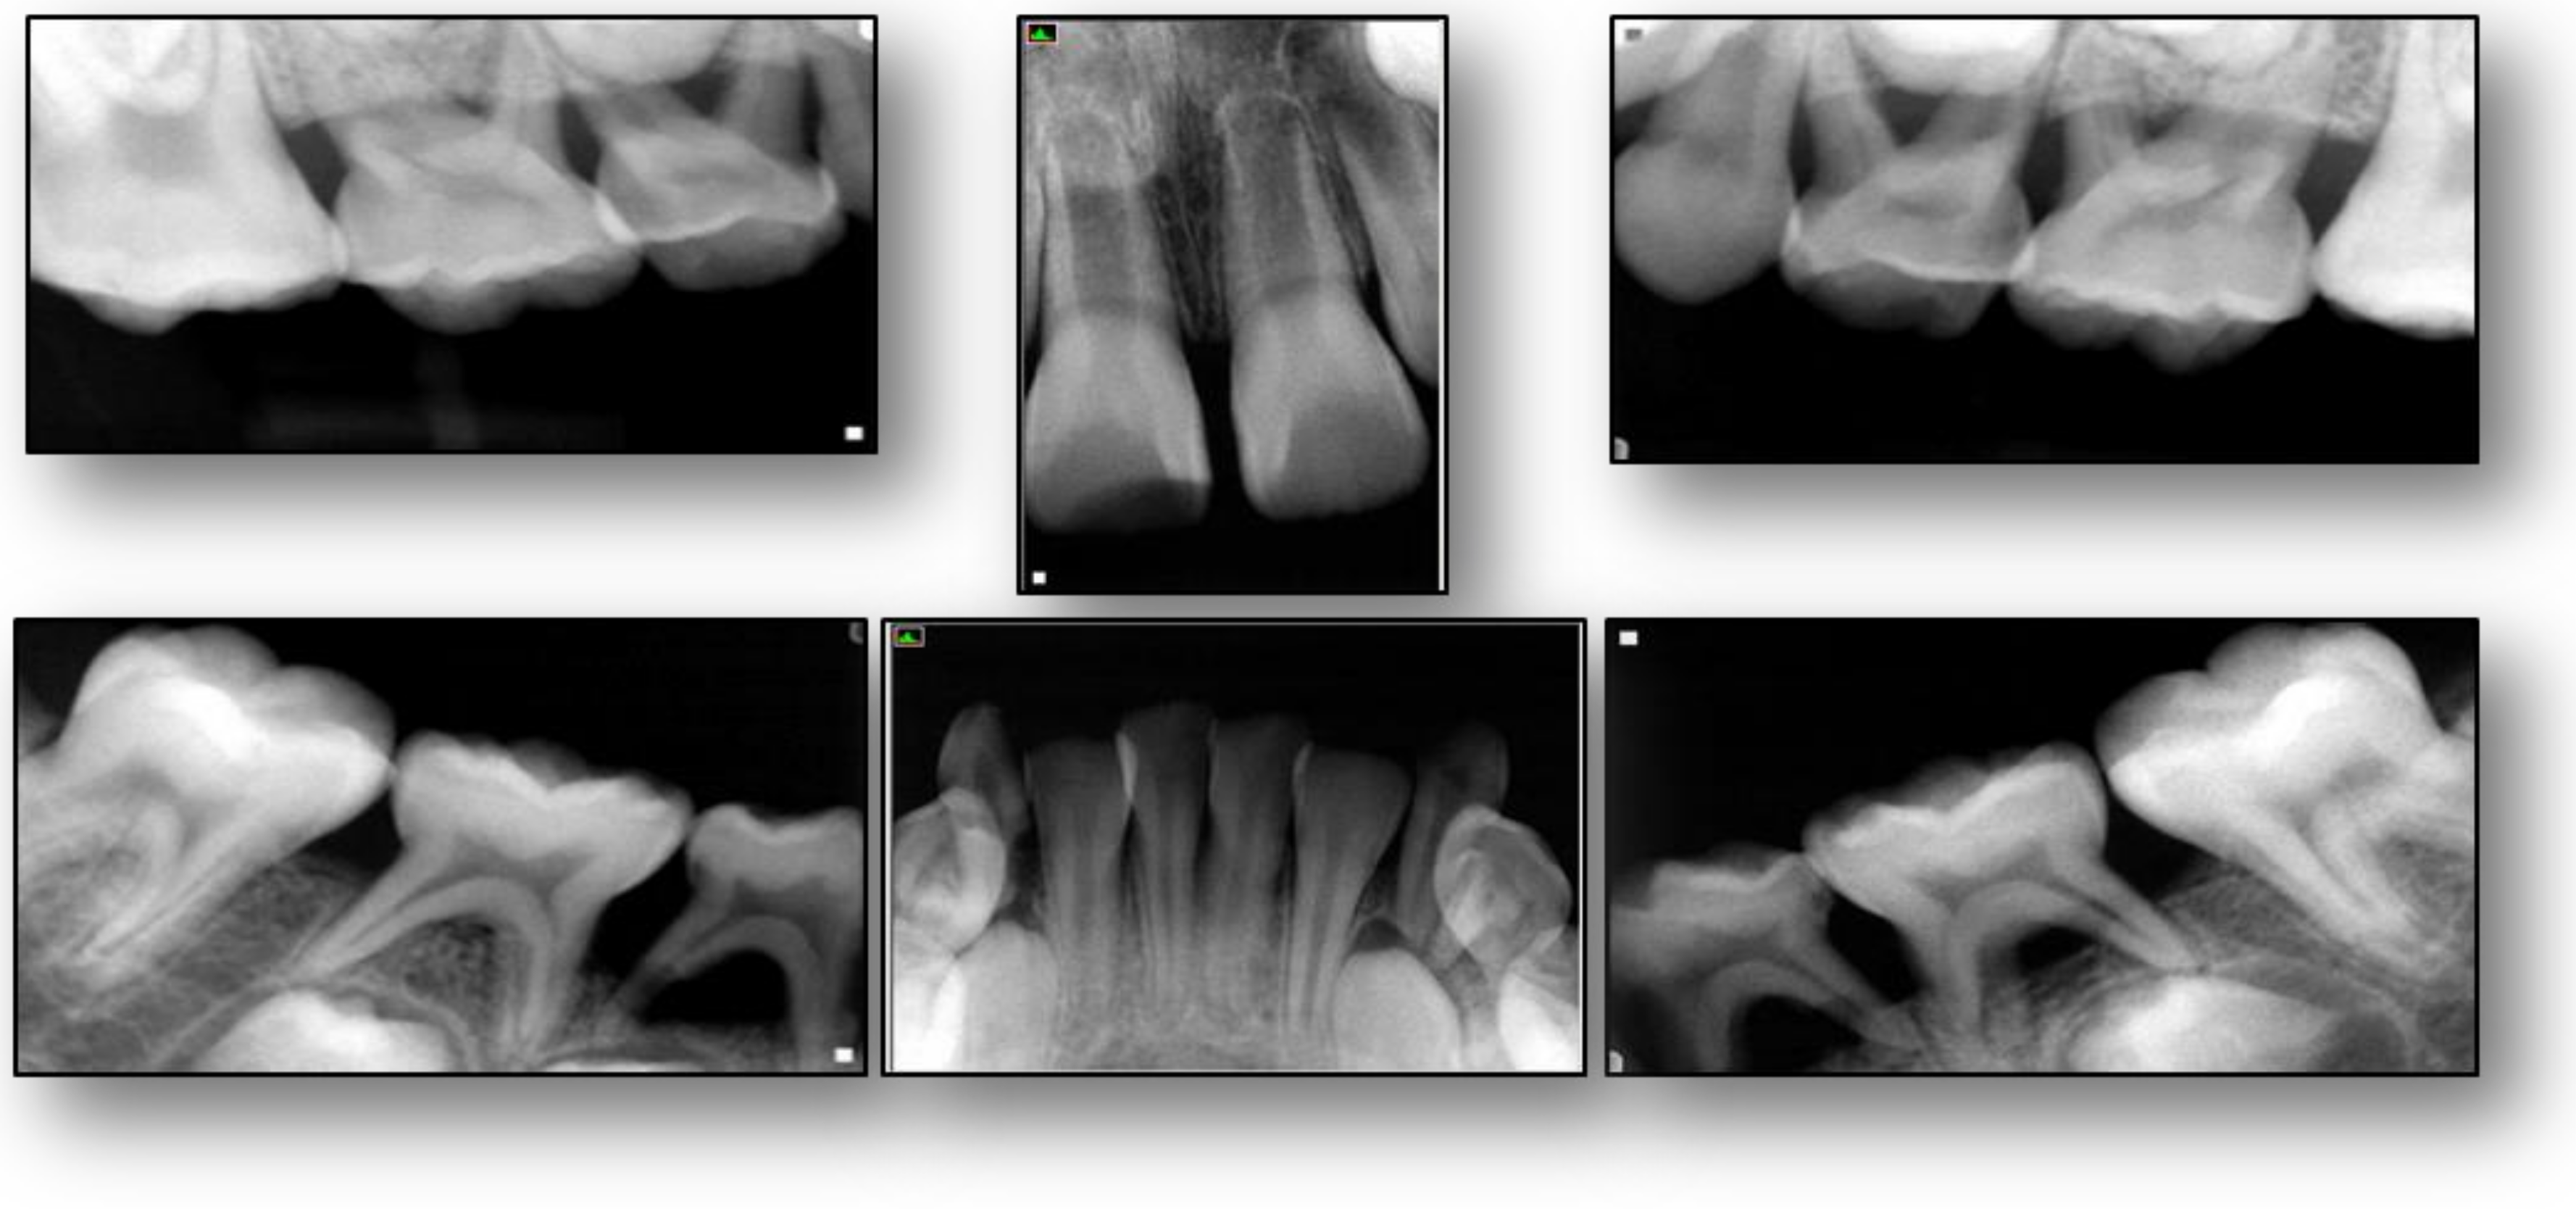

2. Case Presentation